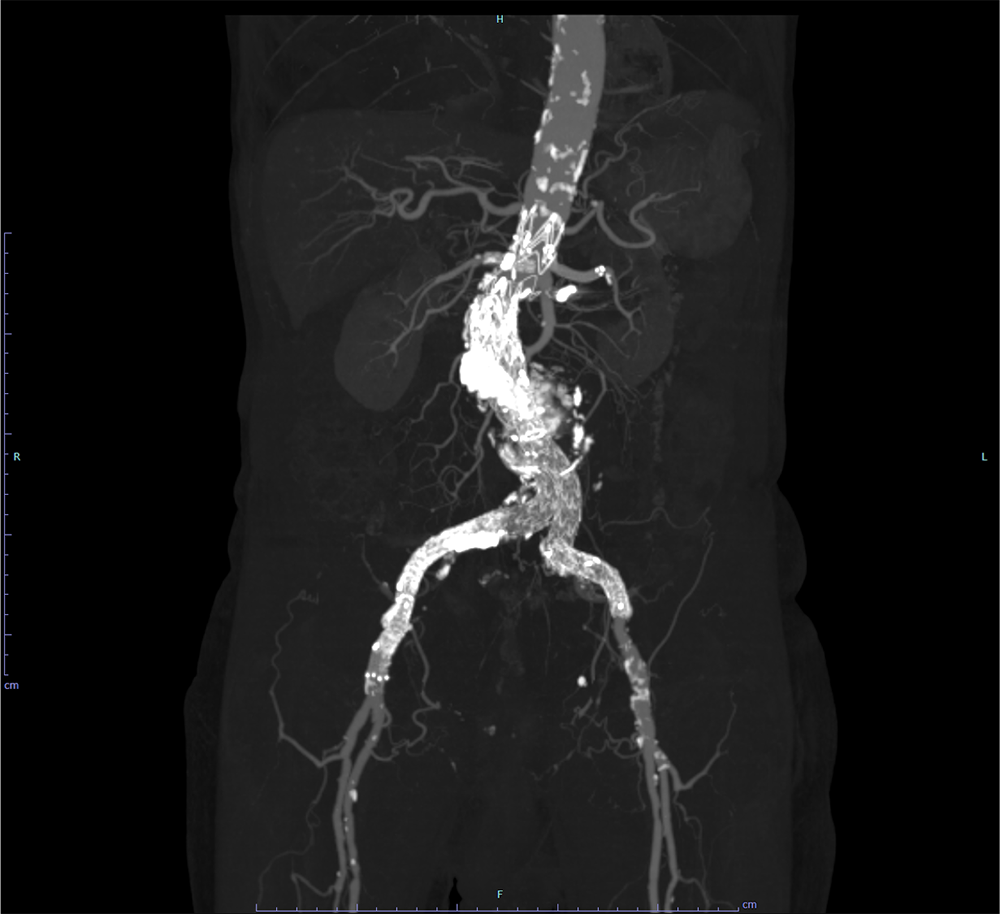

EVAR後の腹部大動脈瘤破裂に対し追加EVARを施行した一例

当科で腹部大動脈瘤に対しEVAR術後、瘤増大傾向で外来フォローアップされていた。急激な腹痛で来院し造影CTが撮影された。瘤内にType1aエンドリークを認めるほか、瘤内解離、破裂を認めた。緊急で追加EVARが行われ、治療後エンドリークは消失し、術後経過も問題なく退院となった。

腹部大動脈瘤(AAA)の診断と治療戦略の決定において、造影CTは最も信頼性の高い検査である。造影CTにより瘤の存在部位や最大径、長さ、形状を正確に評価でき、拡大速度や形態の異常といった破裂リスクの判定にも用いられる。また、瘤壁の不整、壁在血栓、壁内血腫の有無を描出することで、切迫破裂や破裂の診断に直結する。さらに、腎動脈・内腸骨動脈・下腸間膜動脈など主要分枝との位置関係を明らかにすることで、開腹術かEVARかといった治療適応の判断やステントグラフトのデザイン決定に不可欠である。未破裂AAAの経過観察にもCTが推奨されており、腹部超音波に比べ測定誤差が少ない一方、腎機能障害などの可能性を考慮する必要がある。破裂または切迫破裂が疑われる場合には、後腹膜血腫や造影剤漏出を迅速に描出し、緊急治療の判断に直結するため、診断と治療計画の双方において中心的役割を担う。